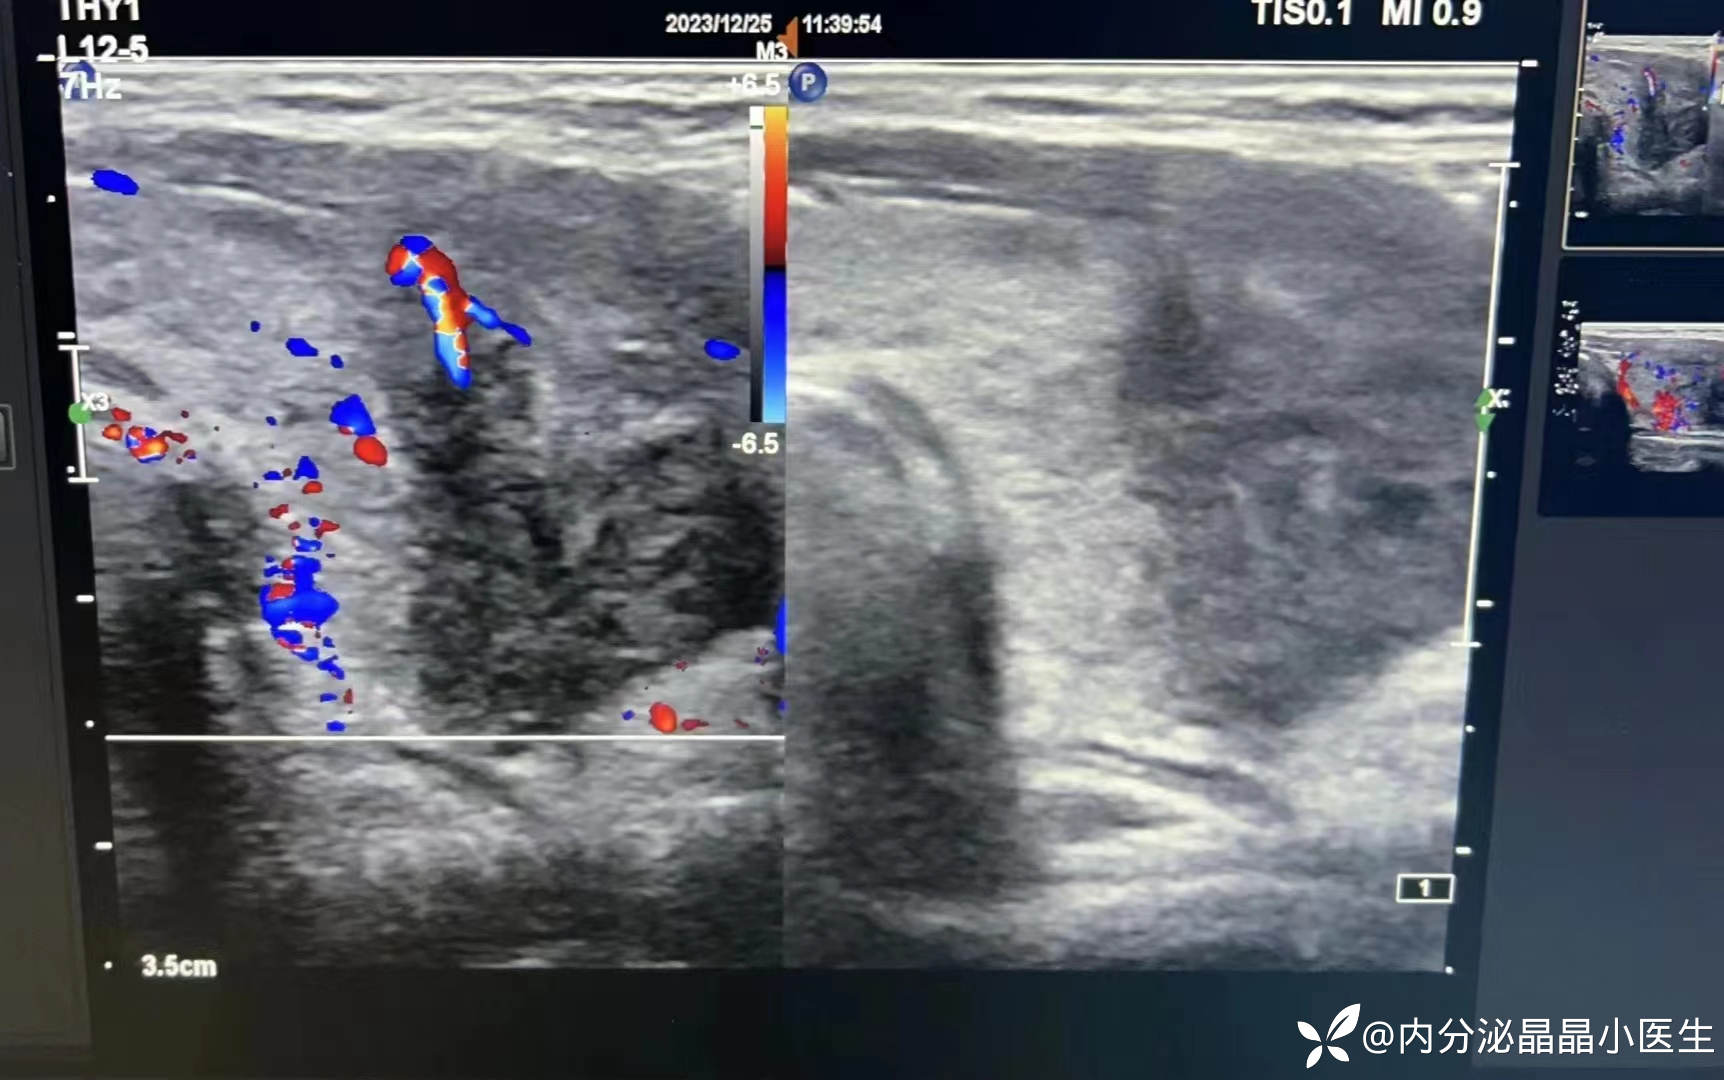

简要病史:1周前“感冒后”出现发热,乏力,体温波动在37.8-38.5℃之间,口服“三九感冒冲剂”、“塞来昔布、布洛芬后”后体温可下降,未重视。逐渐出现颈部疼痛,乏力加重,食欲下降,体温持续波动在38-39℃之间,体重进行性下降,出汗、心慌,手抖,查甲功提示甲状腺毒症,血沉71mm/h,TRAb阴性,肝功能轻度异常,甲状腺超声提示亚甲炎。

临床诊断:亚急性甲状腺炎